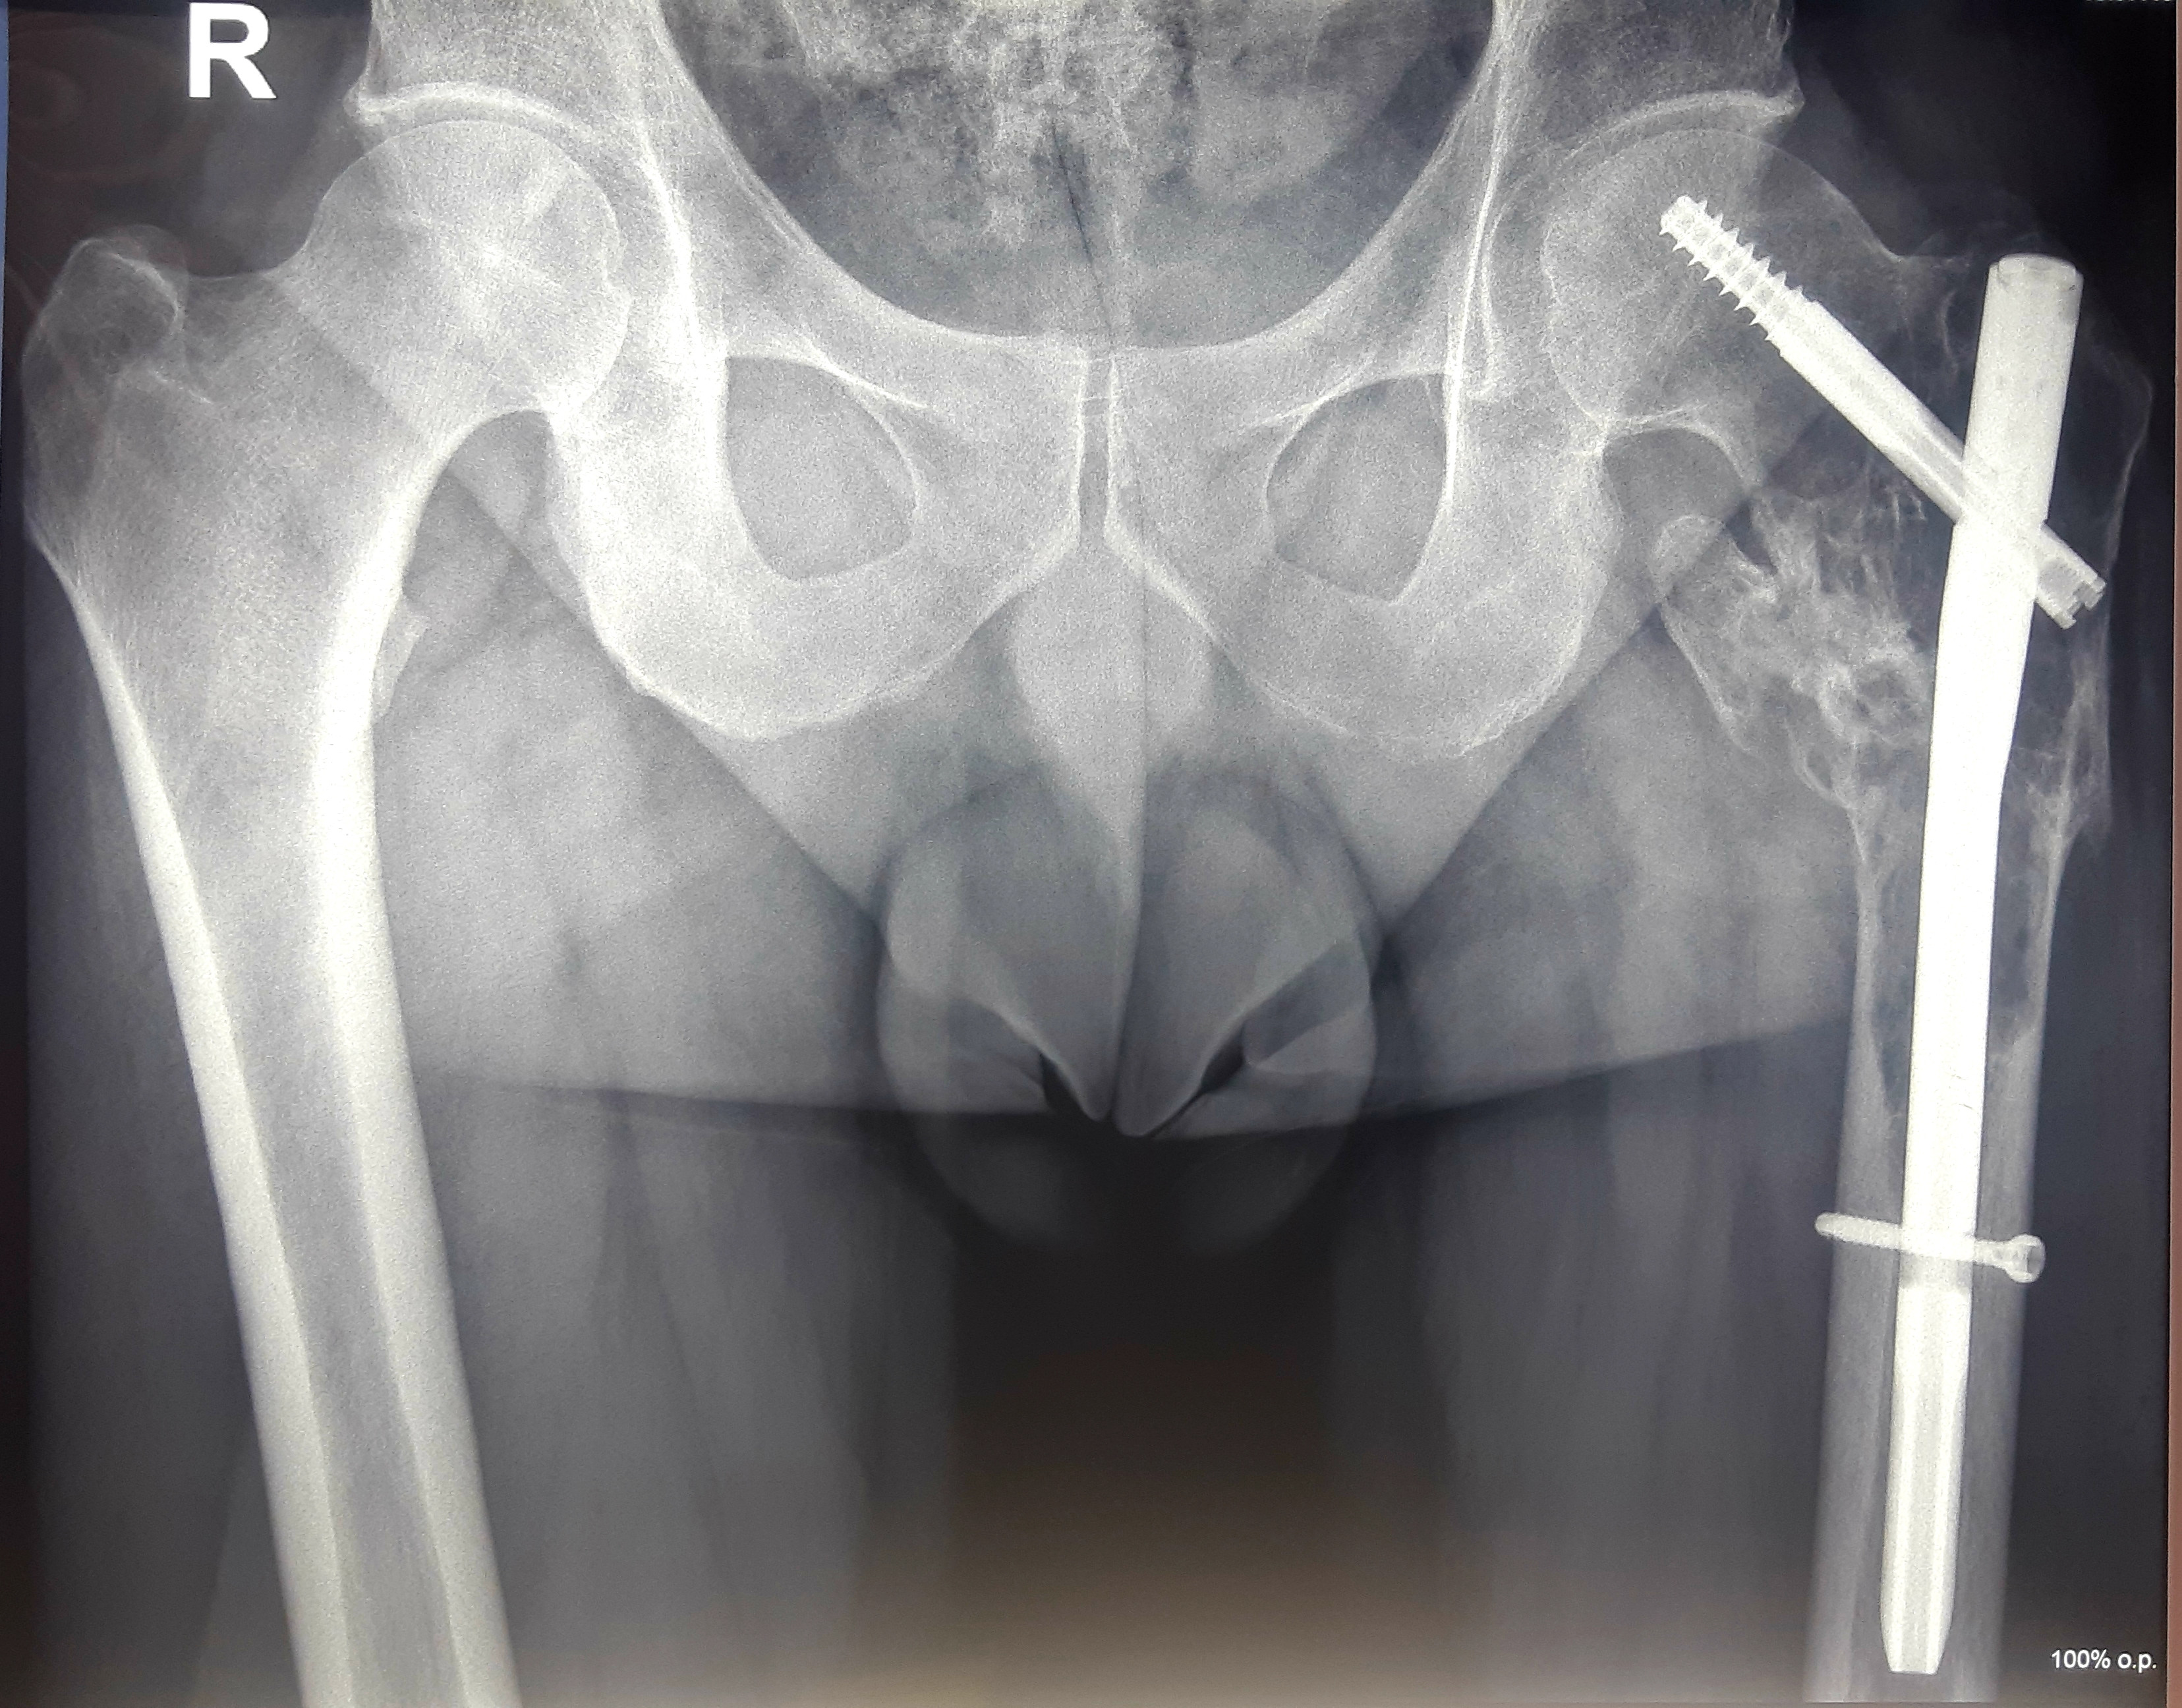

1. Солитарная плазмоцитома верхней трети бедренной кости.

После хирургического лечения в одной из зарубежных клиник по поводу перелома бедренной кости, как впоследствии оказалось, вторичного характера, 40-летний пациент обратился в МЦ ''Наири''.

В ходе обследования была диагностирована солитарная плазмоцитома.

После проведения предоперационной химиотерапии пациент был прооперирован – была произведена сегментарная резекция верхней трети бедренной кости, образовавшийся дефект был замещен индивидуальным биполярным эндопротезом бедренной кости и тазобедренного состава, изготовленным на заказ в Европе. В результате проведения органосохранного лечения удалось сохранить функционирующую конечность пациента.

До операции